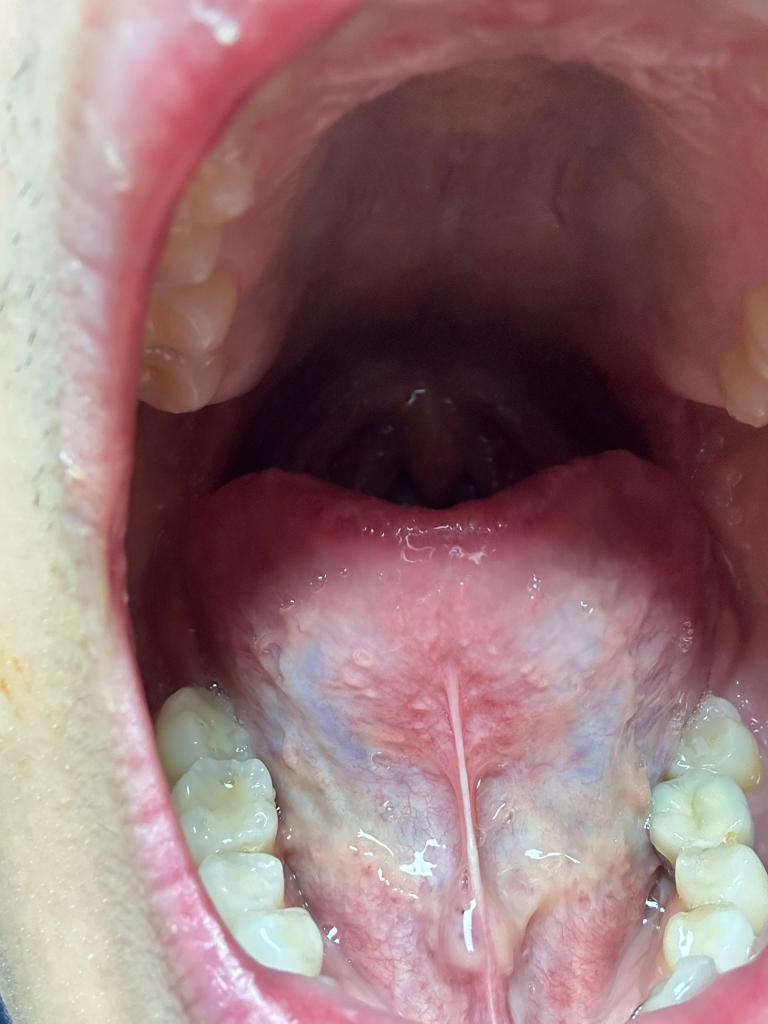

혹시 혀밑에 이거 침샘일까요?

모양이 왜이렇게 볼록한지 모르겠네요 저기가 침샘이라 그런걸까뇨? 모양이 이상하진 않나요?

혹시 이상 소견이 있을까요? 병원를 가야하는건지 정상인지 불편함은 없습니다.

• 1번 째 사진

혀밑샘의 침이 분비되는 구멍이 있어서 저렇게 볼록하게 생겼습니다. 정상적인 모습입니다.